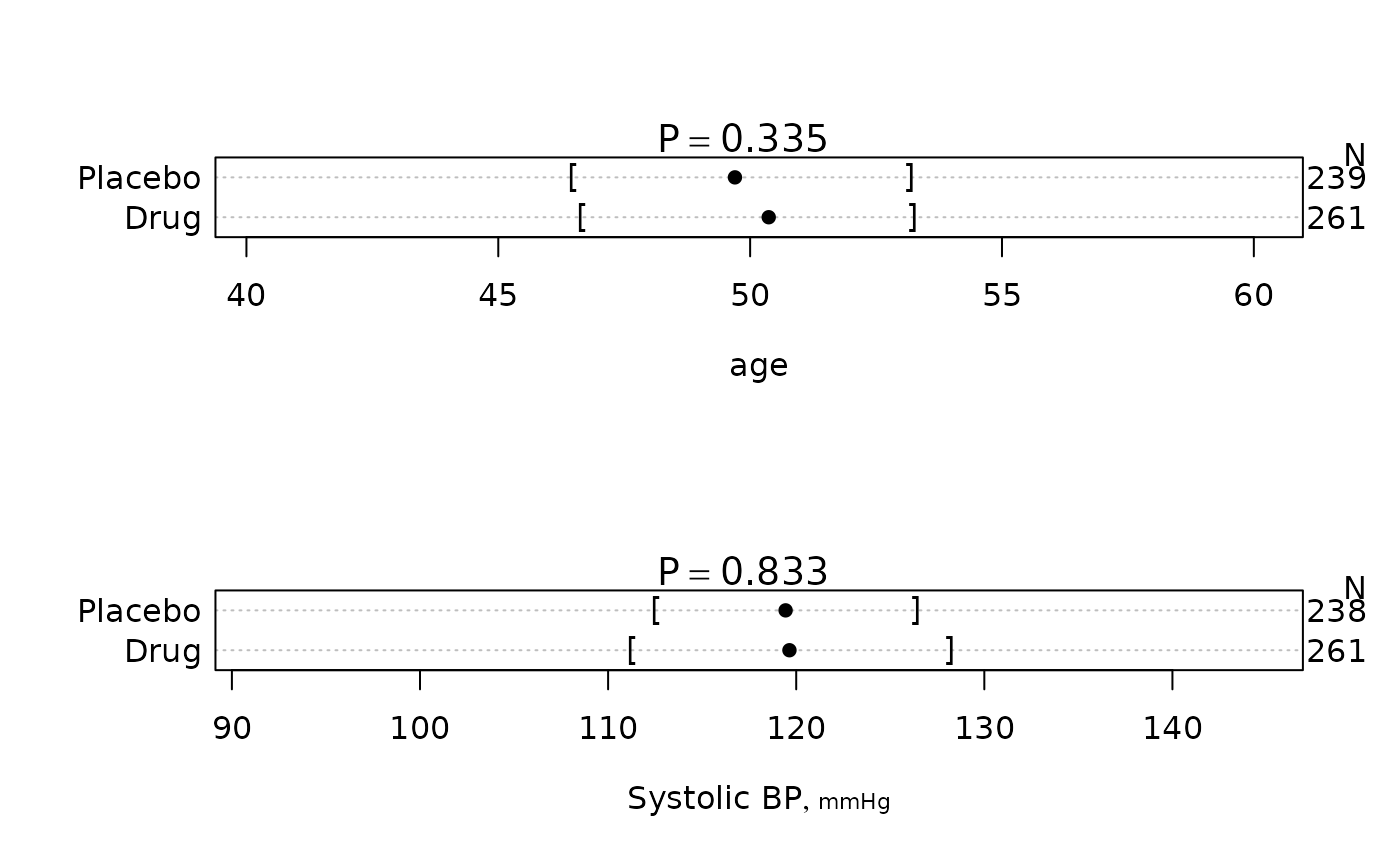

f <- summaryM(age + sex + sbp + Symptoms ~ treatment, test=TRUE)

#> |age |500| 46.7/50.4/53.2| 46.5/49.7/53.2| F=0.93 d.f.=1,498 P=0.335 |

#> |Systolic BP [mmHg] |499| 111/120/128 | 113/119/126 | F=0.04 d.f.=1,497 P=0.833 |

plot(f, conType='dot', prtest='P')

plot(f, conType='dot', prtest='P')